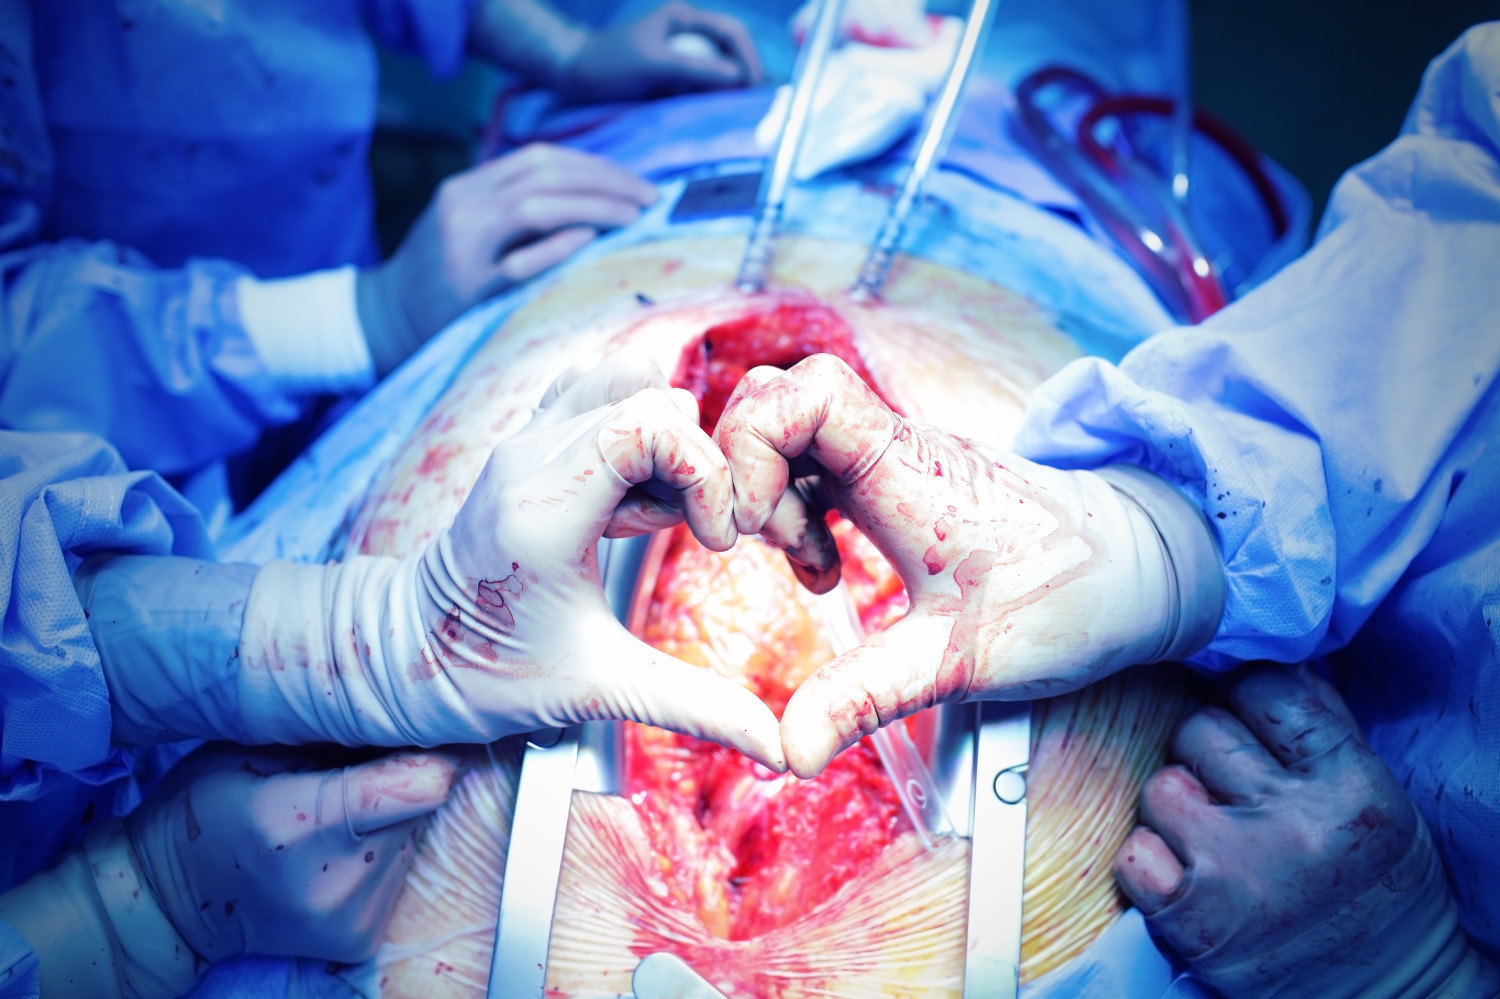

Сроки проведения повторного вмешательства на сердце не влияли на смертность

Ученые из Научно-исследовательского института Лернера оценили влияние сроков проведения повторных кардиальных вмешательств на операционную смертность и сложность используемых процедур. Результаты исследования опубликованы в журнале JAMA и на портале Medscape.

Анализ показал, что не наблюдалось существенной разницы в показателях операционной летальности между ранними повторными вмешательствами (3,6%) по сравнению с операциями спустя 1—5 лет (3,1%), 5—15 лет (3,4%) и более 15 лет (3,2%).

По словам исследователей, увеличение смертности наблюдалось среди отдельных случаев повторного аортокоронарного шунтирования в течение первого года; однако небольшое количество смертей в этой группе не позволило сделать окончательные выводы о наличии этой связи. Ранние повторные вмешательства оказались связаны с повышенной хирургической сложностью, более длительным временем операции (в среднем 402 минуты), большей потребностью в интраоперационном переливании крови (77%) и высоким анатомическим риском (12%).

Наиболее распространенными факторами, связанными с операционной смертностью, были внеплановое хирургическое вмешательство, более низкие уровни гематокрита, более высокие уровни креатинина, более высокий функциональный класс по классификации Нью-Йоркской кардиологической ассоциации и более низкая фракция выброса левого желудочка.

Анализировали данные о 6021 повторном кардиологическом вмешательстве с рестернотомией. Операционная летальность оценивалась для четырех временных интервалов с момента предыдущей операции: менее одного года (ранние повторные операции), 1—5 лет, 5—15 лет и более 15 лет. Хирургическая сложность оценивалась по продолжительности процедур и количеству необходимого переливания крови.